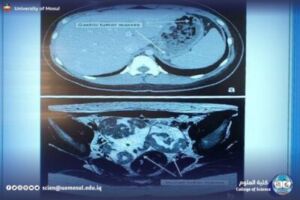

During the course, the basic principles of medical imaging were explained such as contrast, accuracy, the principle of operation of each device, the physics of the device, and how to read the images resulting from a device. Then move on to display the following most important devices in a simplified form:

CT: an explanation of how to take multiple clips, the idea of the HU, and its role in imaging the brain, abdomen, and lung.